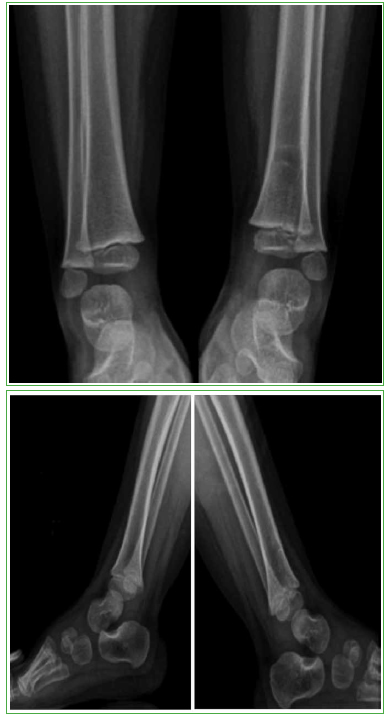

Lipoblastoma: una causa inusual de tumoración del pie en niños

65-73

Acceso mediante suscripción PDF Acceso mediante suscripción PDF_EN (English) Acceso mediante suscripción Figura 1 Acceso mediante suscripción Figura 2 Acceso mediante suscripción Figura 3 Acceso mediante suscripción Figura 4 Acceso mediante suscripción Figura 5 Acceso mediante suscripción Tabla 1 Acceso mediante suscripción HTML